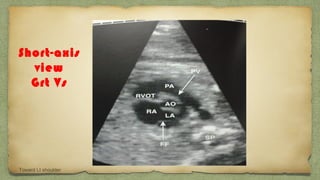

On Slight angulation

Towards rt shlder

Short-axis

view

Grt Vs